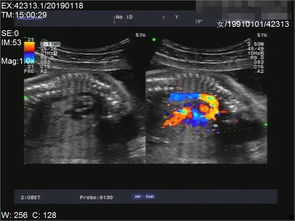

系统B超检查,也称为胎儿系统B超检查或产科III级检查,是一种重要的产前检查手段。它通过彩色多普勒超声技术对胎儿进行全面扫描,以评估胎儿的发育情况,并检查胎盘、羊水和腹腔内脏器的发育状况。以下是关于系统B超检查的一些详细信息:

系统B超检查可以采用彩超和四维超声进行检查。四维超声可以提供更清晰、更立体的图像,有助于医生更准确地判断胎儿的发育情况。